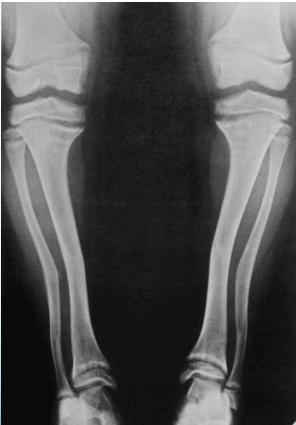

Radiological Features

Primary X-ray Findings

- Widened physis (first and most prominent finding)

- Metaphyseal changes:

- Cupping (due to weak new bone)

- Irregular margins

- Deformed bones